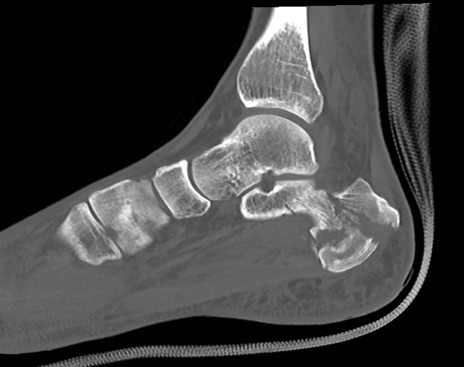

症例37 左足関節CT(矢状断像)

左足関節CT

冠状断像